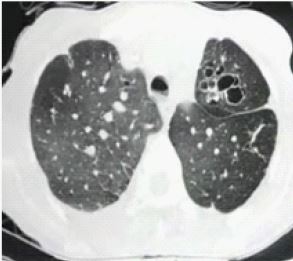

Figure 2: High resolution computer tomography of thorax- bronchiectasis in left upper lobe.

A 35-year-old male was admitted to the hospital for productive cough and episodic breathlessness and rhinitis. He had history of increase of symptoms with seasonal variation and on exposure to cold. He had been diagnosed with AAAA syndrome including achalasia cardia, alacrimia, and adrenocortical insufficiency, autonomic and peripheral neuropathy since 5 years of age. He had past history of tuberculous meningitis at 6 years of age managed with 1 year of antituberculosis treatment. He also had history of hospitalization several times for cough and fever treated symptomatically associated with relief of symptoms. Physical examination detected Alacrimia, anisocoria, dysarthria, microcephaly, generalized hyperpigmentation and nasal speech. His pulse rate, respiratory rate, blood pressure and transcutaneous oxygen saturation were 90 per minute, 20 per minute, 110/70 mmHg and 93% in room air respectively. Bilateral crackles on upper lobe areas were heard on auscultation. Results of full blood counts were as follows: hemoglobin 11.5 g/dl, hematocrit 33.5%, white blood cell count 7500 /mm3, 78% segmented neutrophils, 3% monocytes, 23% lymphocytes and 2% eosinophils and biochemistry analysis within normal limits. Serum Immunoglobulin E was 43.92 IU/ml. Plain chest radiograph revealed no abnormality. High-resolution computer tomography revealed centrilobular nodules with fibro bronchiectactic changes in bilateral upper lobes with mosaic attenuation in bilateral lung fields. Sputum for cartridge based nucleic acid amplification test did not detect mycobacterium tuberculosis. Sputum was also negative for acid-fast bacilli, AFB smear, culture, and bacterial culture. Spirometry with clinicoradiological correlation was suggestive of obstructive abnormality with forced expiratory volume in 1 second by Forced Vital Capacity (FEV1/FVC) of 68% and FEV1 of 22% predicted with good post bronchodilator reversibility of 29% and 210 ml. Patient was treated with high dose inhaled corticosteroids and long acting beta agonist with oral bronchodilator. Chest physiotherapy with postural drainage was given. Patient improved symptomatically and clinically. Patient was vaccinated for influenza and pneumococcal infection. Diagnosis of Bilateral Bronchiectasis due to AAAA syndrome.

Our patient had clinically important achalasia, which is a part of the AAAA syndrome, causing gastro esophageal reflux and aspiration pneumonia. Achalasia when long-standing results in abnormally dilated esophagus known as pneumoesophagus / megaesophagus if air-filled. The etiology of loss of esophageal myenteric plexus inhibitory neurons still remains unknown. The disease can manifest at any age. Chronic aspiration from megaesophagus may result in respiratory tract infections causing recurrent trauma to the airways and consequent bronchiectasis. Stasis of food in the esophagus and recurrent aspiration seem to play a primary role in Bronchiectasis. Chest radiograph is usually inadequate in diagnosis or quantification of bronchiectasis like in our patient chest radiograph was normal. Chest radiography is relatively insensitive for detection of bronchiectasis. In moderate to severe cases, a “tram-track” appearance of parallel and ring like opacities related to the thickened walls of dilated bronchi and tubular densities related to mucus-filled dilated airways can be seen at chest radiography [9]. However, many cases of bronchiectasis are difficult to appreciate with chest radiography. High-resolution computer tomography is more sensitive than chest radiography and is the reference standard in identification and characterization of bronchiectasis [10] like in our patient high-resolution computer tomography revealed centrilobular nodules and bilateral bronchiectasis. Hence, diagnosis made and with adequate chest, physiotherapy and inhaled long acting beta agonists and corticosteroids patient improved symptomatically and clinically. Recurrent cough with expectorations, recurrent respiratory infections, with symptoms of gastro esophageal reflux it is prudent to look for bronchiectasis as a possibility and investigate even when chest radiography is normal. Bronchiectasis can occur though rare in asymptomatic achalasia cardia secondary to recurrent micro aspiration. Bronchiectasis has severe impact on quality of life resulting from several disease, which makes etiological investigation a complex process demanding special resources and experiences although it has been proved that etiological diagnosis is useful for therapeutic approach.